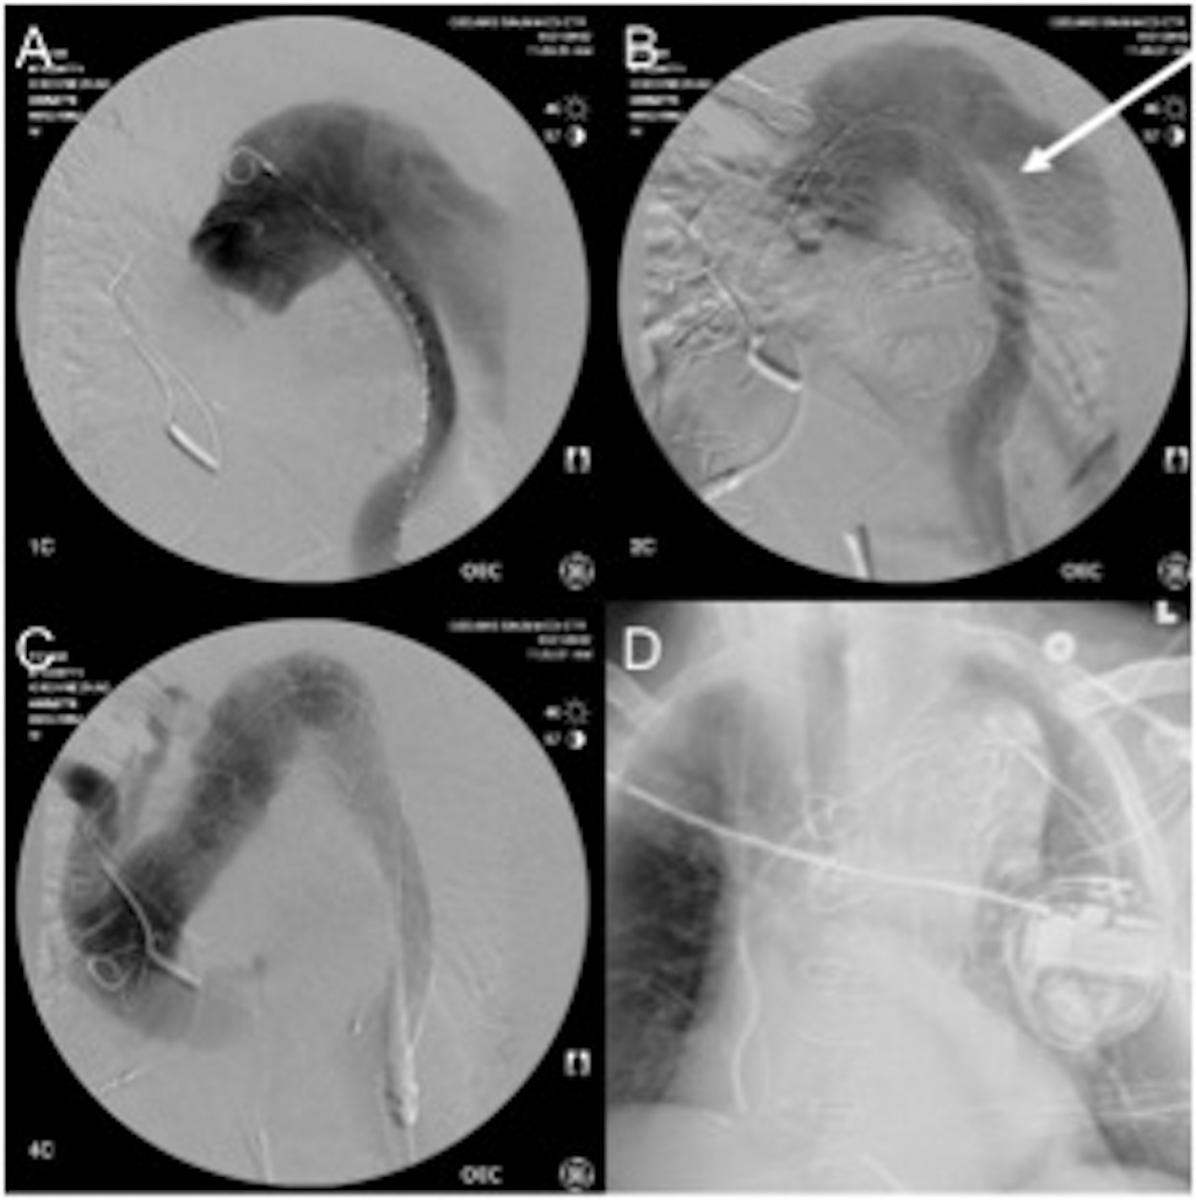

Bilateral femoral artery access was established percutaneously using ultrasound probe and micropuncture technique. A starter wire was advanced under fluoroscopic guidance and placed through the elephant trunk into the ascending aorta using a Simmons 1 catheter. Subsequent intravascular ultrasound interrogation and angiogram using a pigtail confirmed the anatomy (Figure 5A). A “bottom-up” stent grafting strategy was chosen given the significant size mismatch between distal landing zone in mid descending thoracic aorta and the ascending aorta. The first and second stent graft (26 x 22mm and 32 x 28mm, Talent Captivia, Medtronic) were placed in the descending thoracic aorta (Figure 5B). Subsequent exclusion of the transverse aorta was performed using a 36 x 36 x 200mm Valiant Captivia (Medtronic) stent graft (Figure 5C).

An ascending angiogram and intravascular ultrasound imaging confirmed the successful exclusion of the aorta, with lack of blood flow to the false lumen in entire descending thoracic aorta (Figure 5D). The patient remained hemodynamically stable throughout the operation and was transferred extubated to the intensive care unit. His postoperative course was uneventful.

Figure 5: Intraoperative angiogram. A: Preoperative angiogram with the pigtail outside of the elephant trunk. B: Aortogram after deployment of the Talent stent grafts with perfused false lumen. C: Completion angiogram with no endoleak. D: Postoperative X-ray of the chest with the stent graft and the AICD.